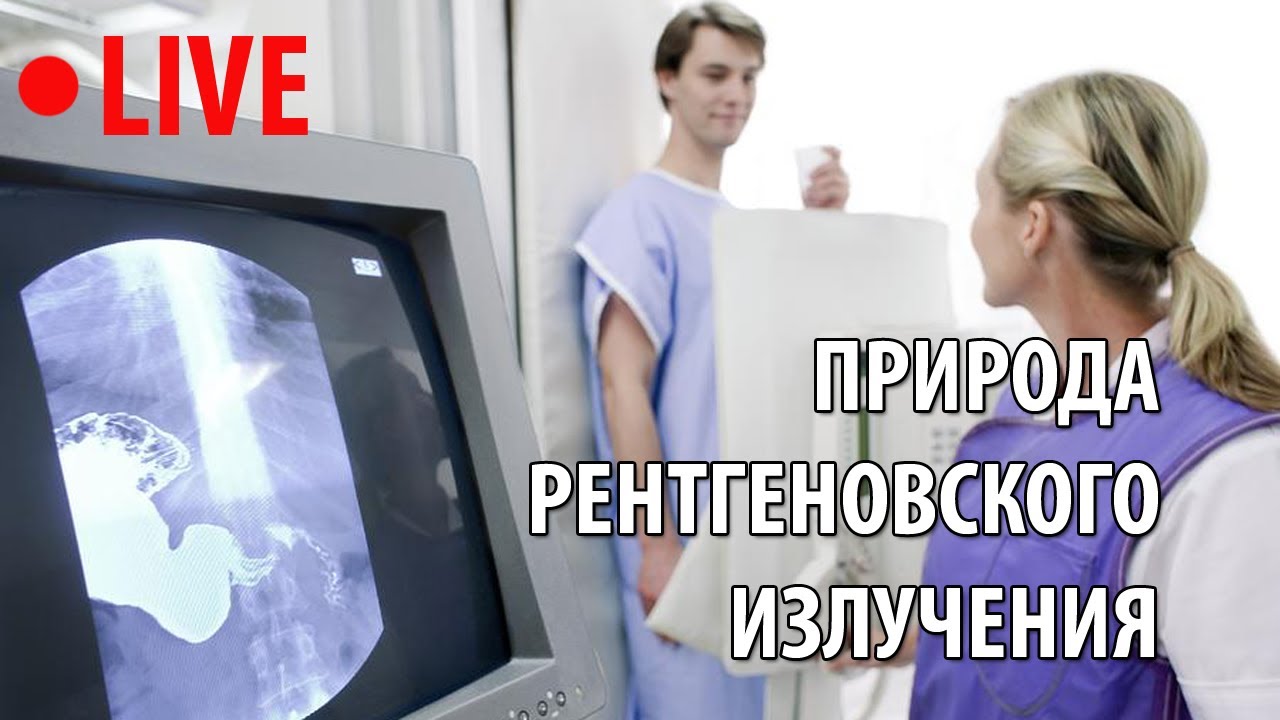

Процедура рентгенологического исследования

Следуйте указаниям рентгенолога для правильного позиционирования тела.

Рентгенологическое обследование в современном помещении

Рентгеноскопия в IDM Clinic